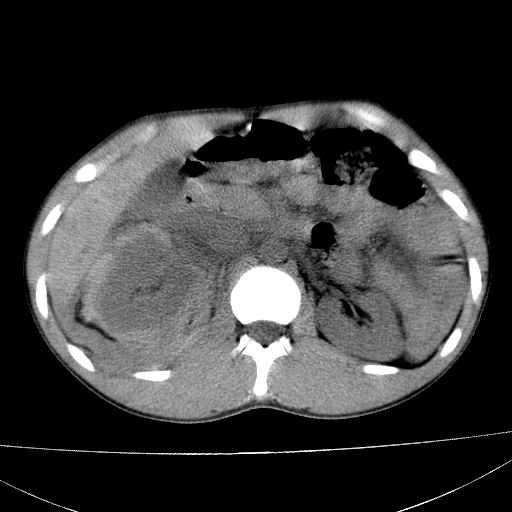

标题: CT15860:男,21岁,腹部外伤2小时伴胸疼。 [打印本页]

标题: CT15860:男,21岁,腹部外伤2小时伴胸疼。

b超示:肝破裂。

肝脏及肾脏明显有损伤性改变并激发腹腔内积液(血),以肝脏撕裂及肾周积血显著。

1)肝破裂伴腹腔积液(血)。2)右肾破裂伴右肾包膜下及肾周血肿。3)腹部空腔脏器穿孔可能。4)右侧少量胸腔积液(血)。

1)肝破裂伴腹腔积液(血)。2)右肾破裂伴右肾包膜下及肾周血肿。3)右侧少量胸腔积液(血)。

肝、右肾包膜下血肿,右侧腰大肌及腹膜后血肿;腹腔少量积血;腹腔疑有少量游离气体伴肠破裂。

1肝挫伤伴腹腔积液。2右肾挫裂伤伴右肾包膜及肾后间隙肿血肿。3右肾脏周围的积气,十二指肠显示结构不清,考虑十二指肠降部破裂可能性大。